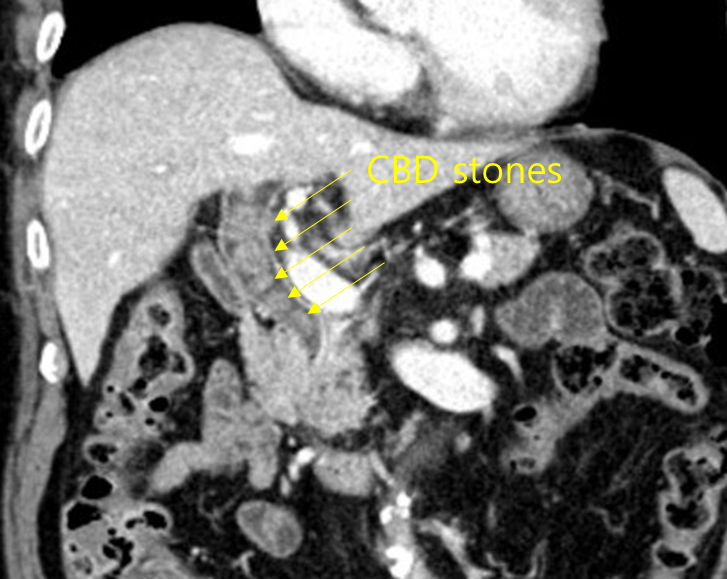

Img | 복부 CT: CBD dilatation, multiple CBD stones |

명치 통증, 발열, 황달의 임상양상과 CT에서 관찰되는 CBD stone으로부터 온쓸개관결석으로 진단한다.

• 통증, 발열, 황달로부터 급성 담관염의 Charcot’s triad를 떠올릴 수 있고, 복부 CT에서는 확장된 담관 안에 다수의 결석이 관찰된다.